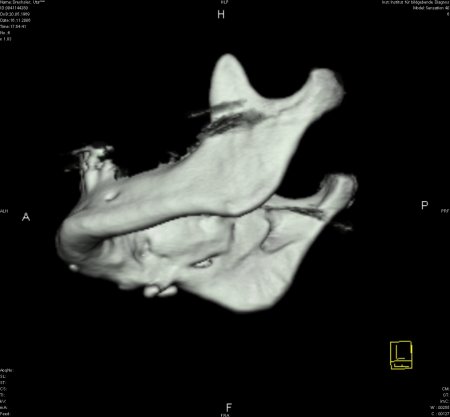

Zur genauen Planung der Kieferkorrektur wurde ich zum CT geschickt. Aus den scheibchenweisen Bildern setzte der Computer ein dreidimensionales Bild zusammen. Dabei ist auch sehr deutlich dieses verlagerte Knochenstück zu sehen.

Zwischenzeitlich stand auch mal die Überlegung im Raum, eine Kinnplastik durchzuführen, bei der die Kinnspitze abgesägt und danach im "richtigen" Winkel wieder aufgesetzt wird. Das klang natürlich auch erst mal ein bissel erschreckend - aber schließlich zählt das Ergebnis. Nach Auswertung der 3-D-Annimation wurde dann allerdings "nur" die erstbeschriebene Kieferkorrektur durchgeführt.